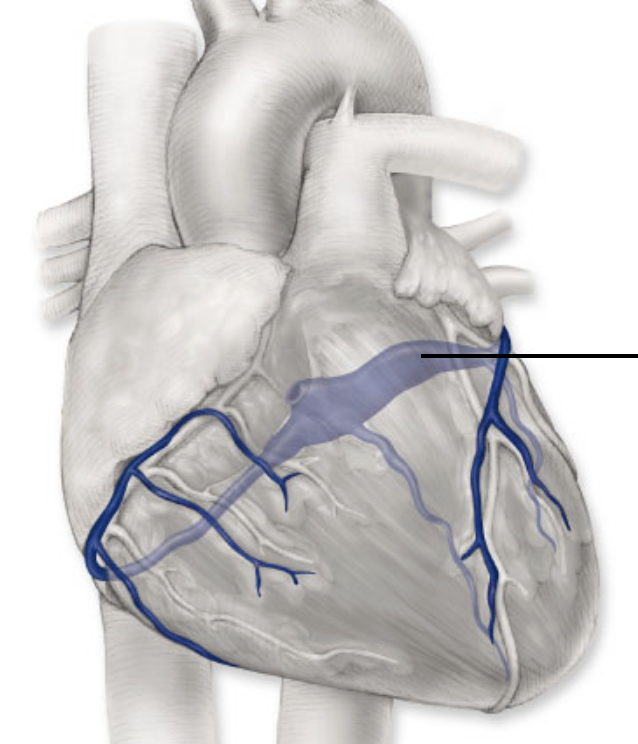

black arrow

inferior vena cava

blue

anterior interventricular artery

pink

circumflex artery

coronary sinus